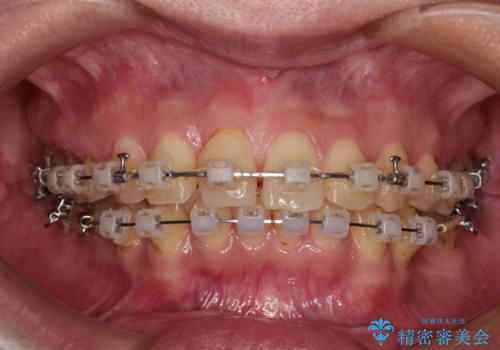

- 矯正装置

- クリアブラケット

- 全体的なデコボコと左下乳歯部の欠損を気にして来院された患者様です。

乳歯が抜け落ちた後の後続永久歯が欠損しているため、スペースが残っておりました。

口元の突出感を気にしているのであれば欠損スペースを利用して抜歯矯正を行うことも可能ですが、横顔の印象はスッキリとしている状態であったため、矯正治療でスペースを閉じきることは不可能と判断し、インプラントによる補綴治療を行うこととしました。